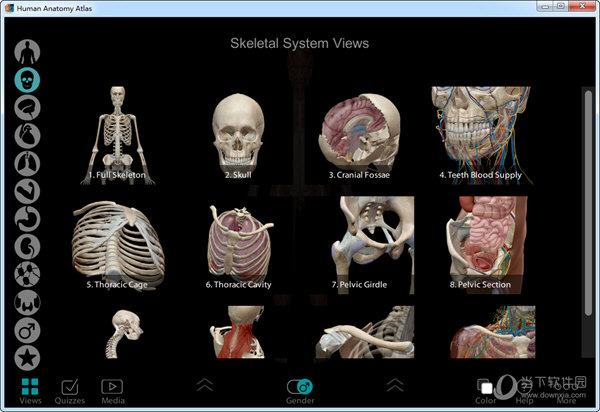

1、提供人体模型查看,可以显示三维模型

6、支持访问视图,收藏夹,测验和动画

8、软件可以添加的内容很多,支持腹部、外展手指、骨骼添加

1、通过左侧的这些功能可以针对人体的神经、骨骼、肌肉进行分层查看学习。